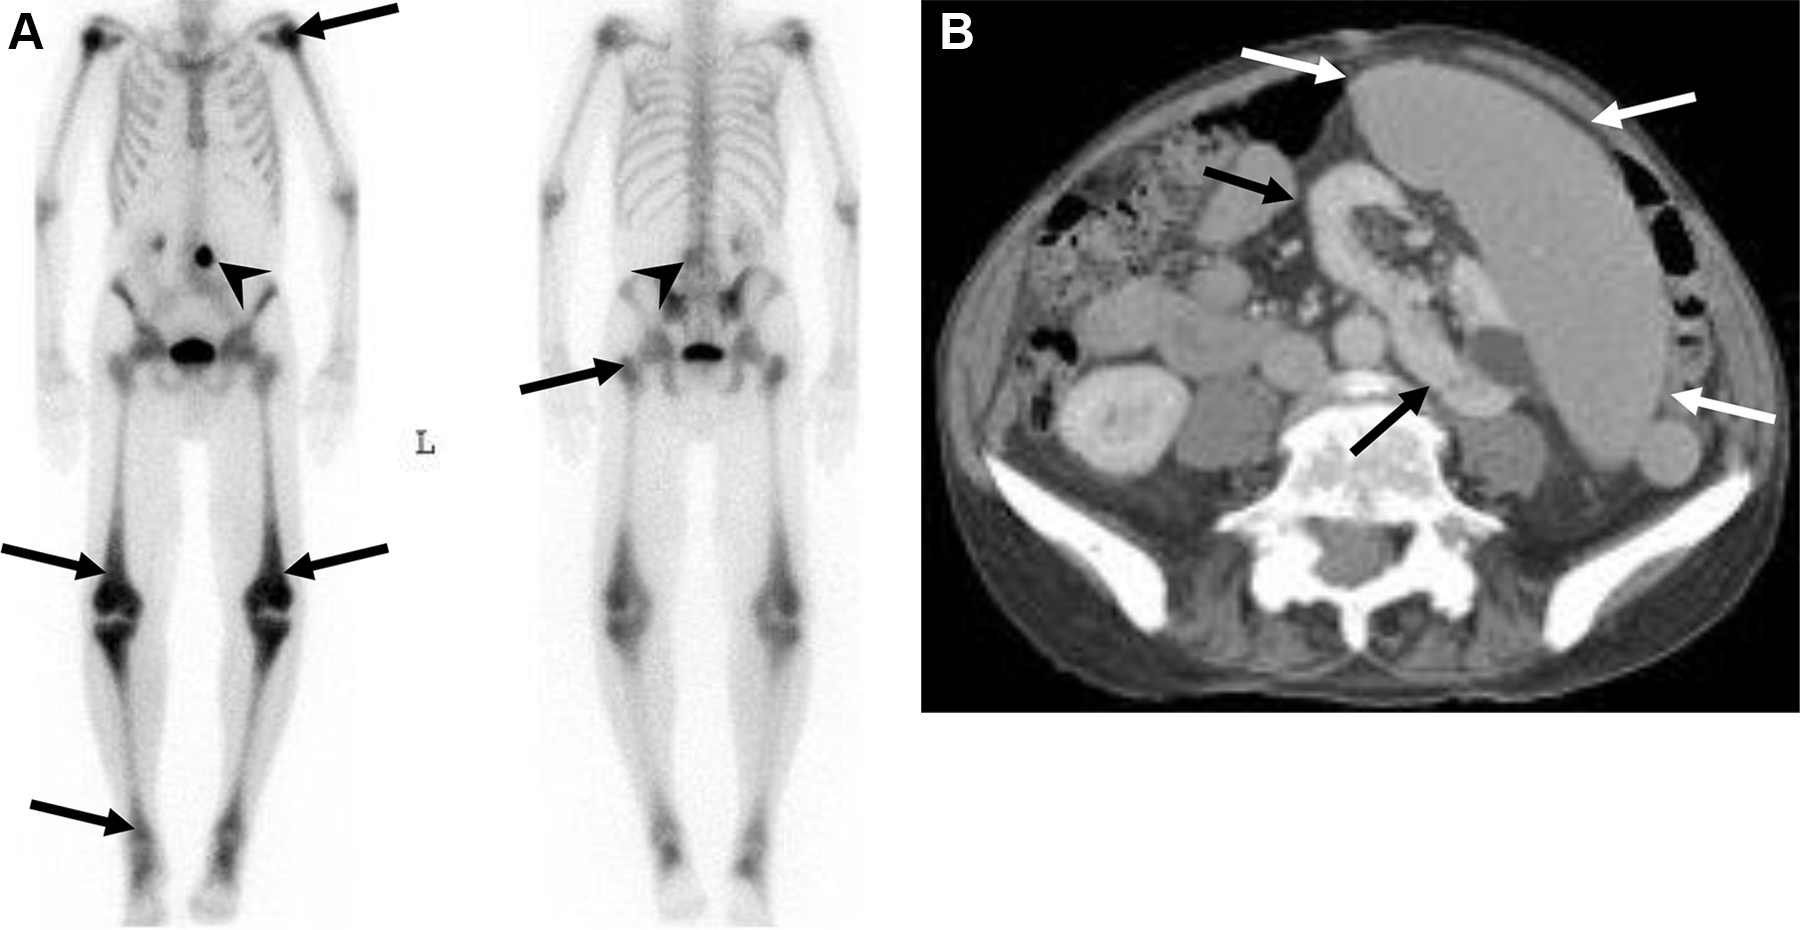

Mielofibrosi in un uomo di 63 anni con peggioramento dell’affaticamento e lieve dolore addominale.

L’esame scintigrafico total body evidenzia un’ipercaptazione diffusa a livello scheletrico, particolarmente intensa nelle regioni epifisarie delle ossa lunghe. Si nota inoltre un evidente dislocamento del rene sinistro verso il basso e medialmente. L’intensa captazione ossea globale può simulare un quadro di “superscan”.

L’imaging morfologico rivela la causa della dislocazione renale sinistra: una splenomegalia massiva, reperto classico dell’emopoiesi extramidollare compensatoria.

Nella mielofibrosi primaria o secondaria, la proliferazione fibrosa all’interno del midollo osseo è spesso accompagnata da una reazione osteosclerotica dell’osso trabecolare, che capta avidamente il radiotracciante osteotropo.